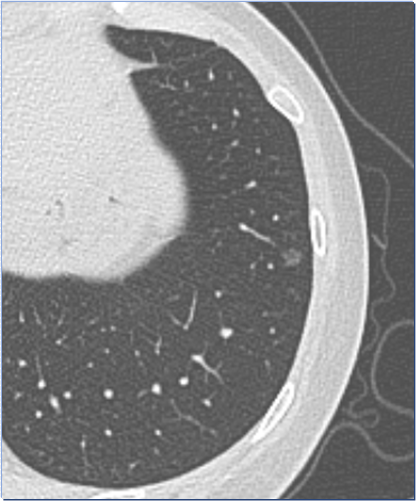

隨著螺旋CT和低劑量薄層CT體檢的廣泛開展,越來越多的肺結(jié)節(jié)被發(fā)現(xiàn)。在人工智能輔助下,體檢篩查肺結(jié)節(jié)發(fā)現(xiàn)率在80-90%.所發(fā)現(xiàn)的肺結(jié)節(jié)中70-80%的肺結(jié)節(jié)是實(shí)性結(jié)節(jié)。這些結(jié)節(jié)都是腫瘤嗎?答案是否定的,腫瘤的可能性只有千分之幾的概率。怎么樣的實(shí)性結(jié)節(jié)需要引起我們的重視?1.年齡在50歲以上、有吸煙史的男子。這類人群是低劑量CT篩查的重點(diǎn)對(duì)象,需要1年1次CT檢查。發(fā)生肺癌的病理類型一般是鱗癌和小細(xì)胞肺癌,腫瘤破壞力強(qiáng),生物學(xué)行為比較“霸道”,可以在半年以上的時(shí)間內(nèi)發(fā)生轉(zhuǎn)移擴(kuò)散,直接進(jìn)入晚期。因此,發(fā)現(xiàn)此類肺結(jié)節(jié)后,需要及時(shí)作出正確診斷,1次誤診或漏診可能會(huì)造成嚴(yán)重后果。相反如果是年輕人、無吸煙史的人群,極少會(huì)發(fā)生這樣的腫瘤。即使發(fā)現(xiàn)“典型”的類腫瘤結(jié)節(jié),首先考慮的也是炎性結(jié)節(jié),而不是腫瘤。??2.職業(yè)致癌物質(zhì)暴露史,如長(zhǎng)期接氡、砷及其化合物等致癌物質(zhì),石棉、二氧化硅和煤煙等。如石棉接觸半年以上即可發(fā)生胸膜增厚及鈣化,并發(fā)現(xiàn)胸膜間皮瘤、肺癌等。這類結(jié)節(jié)往往病史比較長(zhǎng),但是一般會(huì)進(jìn)行常規(guī)的定期職業(yè)體檢。???3.個(gè)人腫瘤史。肺部是其他系統(tǒng)腫瘤轉(zhuǎn)移的常見部位,CT一般表現(xiàn)為多發(fā)實(shí)性結(jié)節(jié),近年來偶也可以看到單發(fā)結(jié)節(jié)(寡轉(zhuǎn)移),呈圓形和橢圓形,無分葉及毛刺,在隨訪過程中進(jìn)行性增大。發(fā)現(xiàn)此類結(jié)節(jié)時(shí),我們一般會(huì)要求提供腫瘤病史,提供血腫瘤標(biāo)志物等,如果兩者均為陰性,基本可以排除轉(zhuǎn)移,高度懷疑時(shí),也可以選擇PETCT檢查。???4.直系親屬肺癌家族史。家族基因的變異,容易導(dǎo)致遺傳,在近年的臨床工作中經(jīng)常被發(fā)現(xiàn)此類病例,比如母親發(fā)現(xiàn)肺癌,其子女進(jìn)行檢查,結(jié)果均發(fā)現(xiàn)有肺結(jié)節(jié),這類多見于腺癌,當(dāng)然很多都是腺體前驅(qū)性病變,也就是以前我們所說的癌前病變。鱗癌病例中也偶有發(fā)現(xiàn)。因此,有直系親屬肺癌史也是危險(xiǎn)因素之一。??5.慢性肺部疾病病史,包括慢性阻塞性肺病、肺結(jié)核和肺纖維化病例。這類病例在CT上有纖維灶、硬結(jié)灶等影像改變,如果在此基礎(chǔ)上發(fā)現(xiàn)肺結(jié)節(jié),并進(jìn)行性增大,首先考慮肺癌。病例分享1病例分享2病例分享3??

日常生活中,總有人八卦說某某人年紀(jì)輕輕,診斷出肺癌半年就掛了;也有講某某人今年體檢發(fā)現(xiàn)了磨玻璃結(jié)節(jié),手術(shù)結(jié)果是肺癌!然后伴隨著一陣嘆息......???事實(shí)真是這樣嗎?答案是否定的,此肺癌非彼肺癌!???我們先來了解下什么是實(shí)性結(jié)節(jié)為表現(xiàn)的肺癌。這種肺癌也是我們老百姓經(jīng)常所說的肺癌,其病理類型可以是鱗癌、腺癌、小細(xì)胞肺癌、大細(xì)胞肺癌、類癌等。以鱗癌為例,鱗癌經(jīng)常發(fā)生在50歲以上、有抽煙史的男子,少見于女性,我們以前統(tǒng)計(jì)的周圍型鱗癌中,男女比例是24:1,在女性患者(3例)中,有2例是抽煙或者曾經(jīng)抽煙的,50歲以下男性的鱗癌也是零星可見的。所以女性如果沒有吸煙史,得鱗癌的機(jī)會(huì)是少之又少;而40歲以下的男性如果是實(shí)性結(jié)節(jié),得鱗癌的機(jī)會(huì)也是少見的;無吸煙史人群也是不太容易得鱗癌的。周圍型鱗癌和腺癌一樣,也會(huì)有原位癌的時(shí)期,但是因?yàn)榘l(fā)生在細(xì)支氣管內(nèi),早期不易發(fā)現(xiàn),但是一旦進(jìn)展,往往有很強(qiáng)的生物學(xué)行為,3個(gè)月可以實(shí)現(xiàn)體積倍增,并呈幾何數(shù)據(jù)生長(zhǎng)。相對(duì)于我們常規(guī)的年度體檢來說,只要漏診或者誤診一次,可能等發(fā)現(xiàn)的時(shí)候就已經(jīng)晚期了,這也是我們老百姓眼中的肺癌。生長(zhǎng)速度快、破壞力強(qiáng)、早期轉(zhuǎn)移是它的特征,所以我們?cè)诎l(fā)現(xiàn)可疑實(shí)性結(jié)節(jié)或者新發(fā)實(shí)性結(jié)節(jié)時(shí),經(jīng)常會(huì)要求患者3個(gè)月內(nèi)復(fù)查一次CT。同樣,如果實(shí)性小結(jié)節(jié)在2年內(nèi)沒有變化,基本也就排除了這種肺癌可能。如果是小細(xì)胞肺癌,可能就更兇險(xiǎn)一些。因此,我們?cè)趯?duì)待這個(gè)類型的肺癌上,越早發(fā)現(xiàn)、越早診斷、越早治療是唯一的方法。??那么以磨玻璃影為特點(diǎn)的腺癌會(huì)出現(xiàn)這種情況嗎?我們把肺腺癌的生長(zhǎng)方式分成2種,一種是實(shí)性結(jié)節(jié)為特點(diǎn),這種病理上生長(zhǎng)方式是以實(shí)體性為主,屬于低分化,和鱗癌一樣,能夠?qū)崿F(xiàn)快速生長(zhǎng)和轉(zhuǎn)移,另一種就是以磨玻璃生長(zhǎng)為主的腺癌,病理上基本就是附壁樣生長(zhǎng)、腺泡樣生長(zhǎng)和乳頭狀生長(zhǎng),在2011年以前我們稱之為“細(xì)支氣管肺泡癌”,屬于高中分化。以磨玻璃影為特點(diǎn)的腺癌,生長(zhǎng)過程中可以分成4個(gè)階段:不典型增生結(jié)節(jié)、原位腺癌、微浸潤(rùn)腺癌和浸潤(rùn)性腺癌。2015年病理分類把不典型增生結(jié)節(jié)和原位腺癌稱為“癌前病變”,2021年的病理新分類中,改為“腺體前驅(qū)性病變”,這個(gè)階段還不是癌,病灶沒有侵襲力和破壞力,長(zhǎng)期復(fù)查不變;微浸潤(rùn)腺癌是在原位腺癌的基礎(chǔ)上,病灶中出現(xiàn)浸潤(rùn)性成分“小于等于5毫米”,這個(gè)階段病灶侵襲力比較低,也可以保持長(zhǎng)期不變,以往的文獻(xiàn)中指出,原位腺癌和微浸潤(rùn)腺癌5手術(shù)后五年生存率可以達(dá)到或接近100%,在現(xiàn)在看來可能就是笑話,因?yàn)檫@類病變?nèi)绻皇中g(shù),5年內(nèi)大多數(shù)也不會(huì)有變化的;浸潤(rùn)性腺癌指浸潤(rùn)成分超過了5毫米,這個(gè)時(shí)期其生長(zhǎng)也可以比較緩慢,但是長(zhǎng)期隨訪可能會(huì)出現(xiàn)微乳頭或者實(shí)體生長(zhǎng)成分,導(dǎo)致病變快速發(fā)展或者轉(zhuǎn)移,從而危及到生命安全,當(dāng)然,和實(shí)性結(jié)節(jié)為主特點(diǎn)的肺癌比較,其侵襲能力還是略遜一籌。針對(duì)磨玻璃影為特點(diǎn)的肺腺癌生物學(xué)行為,十年來,治療的理念也發(fā)生了非常大的變化,從早診早治到現(xiàn)在的精準(zhǔn)掌握時(shí)機(jī)干預(yù),醫(yī)學(xué)上也走過了一段坎坷的路。比如十年前,我們手術(shù)病理證實(shí)了肺原位癌,就認(rèn)為挽救了一條生命,但是現(xiàn)在我們發(fā)現(xiàn)肺原位腺癌經(jīng)過十年隨訪,還是沒有變化(救人?害人?);國(guó)外大數(shù)據(jù)統(tǒng)計(jì)中,根據(jù)其影像學(xué)的表現(xiàn),手術(shù)指證基本也是掌握在微浸潤(rùn)向浸潤(rùn)過渡的時(shí)期,而對(duì)于普通比較輕微的微浸潤(rùn)、原位腺癌都是鼓勵(lì)隨訪。??綜上,以磨玻璃影為特點(diǎn)的腺癌和實(shí)性結(jié)節(jié)為特點(diǎn)的肺癌是兩回事,兩者在預(yù)后上有明顯的區(qū)別!科學(xué)在不斷的進(jìn)步,醫(yī)學(xué)的認(rèn)識(shí)也是在不斷更新,相信在不久的將來,肺癌的認(rèn)識(shí)和診治上一定也會(huì)取得更大的進(jìn)步,進(jìn)一步造福人類!